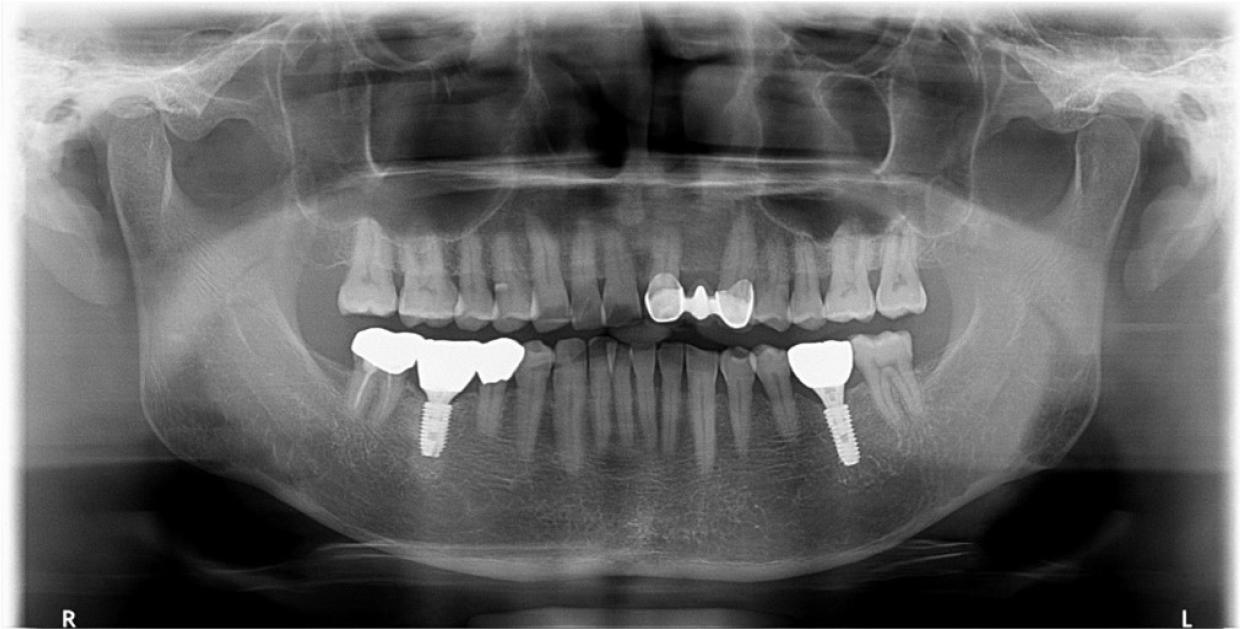

A 55-year-old man visited the clinic for implant discomfort and bleeding. The implant in the lower right 1st molar was placed three years ago at a private practice and was found to exhibit symptoms of buccal mucosal swelling and mesio-buccal deep probing pocket (Table 1). A sclerotic line on the fixture middle level was observed on panoramic and periapical radiographs (Figs. 1 and 2). There was no mobility or pus discharge but a throbbing pain during function. The probing depth was 10 mm; therefore, he was diagnosed with peri-implantitis, and we recommended implant removal. Patient hoped preservation, so regenerative therapy were preceded.

An implant of 5.0 mm diameter and 10.0 mm length (Luna®; Shinhung, Seoul, Korea) was placed at the lower right 1st molar site, and the implant stability quotient (ISQ) was 81. The Φ6.0 × 5.0 mm healing abutment was placed and sutured with 4-0 Supramid® (Assut Medical Sarl, Pully-Lausanne, Switzerland) (Fig. 11). It showed stability on the post-operative panoramic radiograph (Fig. 12). After 4 months, the final prosthesis was completed (Figs. 13 and 14).

At 5 years follow-up, the implant showed stable alveolar bone without any signs of peri-implantitis or bone resorption on the radiograph analysis (Figs. 15 and 16). In addition, there was no bleeding on probing and no clinical problems.